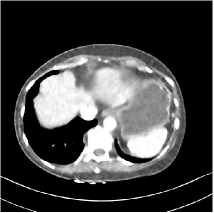

Refer to caption WavResNet [11]Refer to caption WavResNet [11]Refer to caption WavResNet [11]Refer to caption Momentum-Net (SimpleCNN)Refer to caption Momentum-Net (SimpleCNN)Refer to caption Momentum-Net (SimpleCNN)Refer to caption Momentum-Net (SimpleCNN-RSN)Refer to caption Momentum-Net (SimpleCNN-RSN)Refer to caption Momentum-Net (SimpleCNN-RSN)Refer to caption Momentum-Net (Dn-RSN)Refer to caption Momentum-Net (Dn-RSN)Refer to caption Momentum-Net (Dn-RSN)Refer to caption ReferenceRefer to caption ReferenceRefer to caption Reference

Refer to caption Refer to caption Refer to caption Refer to caption Refer to caption Refer to caption Refer to caption Refer to caption Refer to caption Refer to caption Refer to caption Refer to caption Refer to caption Refer to caption Refer to caption

Fig. 3: Three examples (from top to bottom) of the reconstructed testing images using Momentum-Net with SimpleCNN (the second column), with SimpleCNN-RSN (the third column), and with Dn-RSN (the fourth column). The compared WavResNet denoised images are shown in the first column, and the reference images are in the fifth column. See their FBP images in Fig. 4.

3.2 Proposed Momentum-Net with SimpleCNN

Fig. 2 shows that the proposed Momentum-Net with SimpleCNN decreases RMSE dramatically in the first 30 layers, and tends to converge in 50 layers. The Momentum-Net reduces the mean RMSE value by 4.5 HU and gives smaller standard deviations in RMSE, compared to WavResNet, as reported in Table 1. This implies that the proposed Momentum-Net with SimpleCNN can improve both the accuracy and stability of low-dose CT image reconstruction than a state-of-the-art image denoising deep NN, WavResNet. The proposed Momentum-Net with SimpleCNN better removes noise and streak artifacts than WavResNet. It also provides clearer reconstructions of some details; see, in Fig. 3, the boundaries shown in the zoomed region at the top-right corner in the first example, the arrow pointed structures in zoomed areas of the second example, and the arrow pointed tissues in the left zoomed region in the third example.

3.3 Momentum-Nets involving RSN-based training

We show the reconstructed examples by Momentum-Net with SimpleCNN-RSN and Dn-RSN in the third and fourth columns of Fig. 3 respectively. Comparing the first three and the last columns in Fig. 3, we observe that Momentum-Net with SimpleCNN-RSN provides generally noisier reconstructions than WavResNet and Momentum-Net with SimpleCNN. However, Momentum-Net with SimpleCNN-RSN sometimes can provide clearer details than WavResNet. For example, in the right zoomed box of the second example, Momentum-Net with SimpleCNN-RSN shows better reconstruction quality for the arrow pointed structures than WavResNet, and in the left zoomed box in the third row, the former gives clearer small tissues marked by red arrows than the latter. Table 1 reports that Momentum-Net with SimpleCNN-RSN is approximately 2.9 RMSE (HU) higher than WavResNet, while it has smaller standard deviations. This implies that Momentum-Net with SimpleCNN-RSN is more stable than WavResNet, although it may not provide better image qualities. Momentum-Net with Dn-RSN, however, provides the worst visual and numerical results among the compared four methods in this paper.